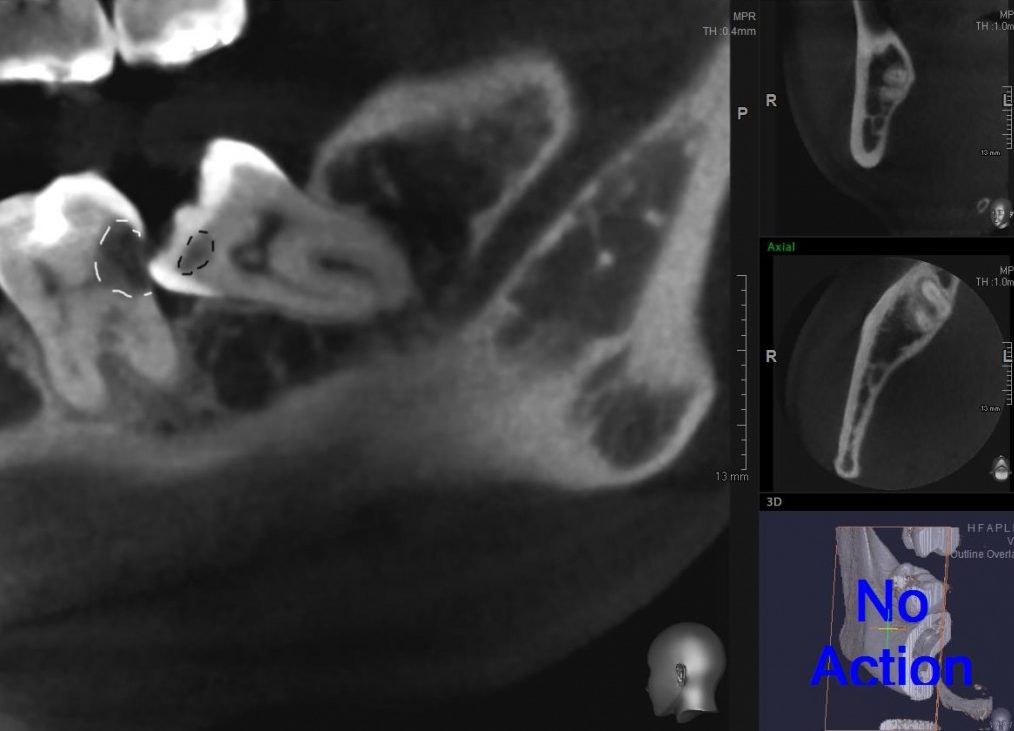

— ортопантомография или, что лучше, конусно-лучевая компьютерная томография. По данным рентгенологического обследования можно определить стадию формирования зуба, направление его движения, отношение к прилежащим структурам, соседним зубам, а также форму и размер образовавшейся под капюшоном полости.

— по данным рентгенодиагностики (КЛКТ или ортопантомограммы) зуб находится в стадии прорезывания (верхушки корней не сформированы), ось прорезывания зуба имеет более-менее правильное направление, его коронковая часть не повреждена кариесом.

— врач-ортодонт подтверждает, что для прорезывания третьего моляра есть необходимое пространство (хватит места в зубном ряду), нет патологии прикуса и признаков развивающейся зубочелюстной аномалии.

— если по данным рентгенологической диагностики причинный зуб имеет сформированную корневую систему, зуб явно уже не прорезывается или, что хуже — упирается коронковой частью в наружную косую линию, соседний зуб или куда-нибудь еще

— если врач-ортодонт после обследования говорит, что в твоем зубном ряду нет места для восьмерок, да еще настоятельно рекомендует тебе исправление прикуса